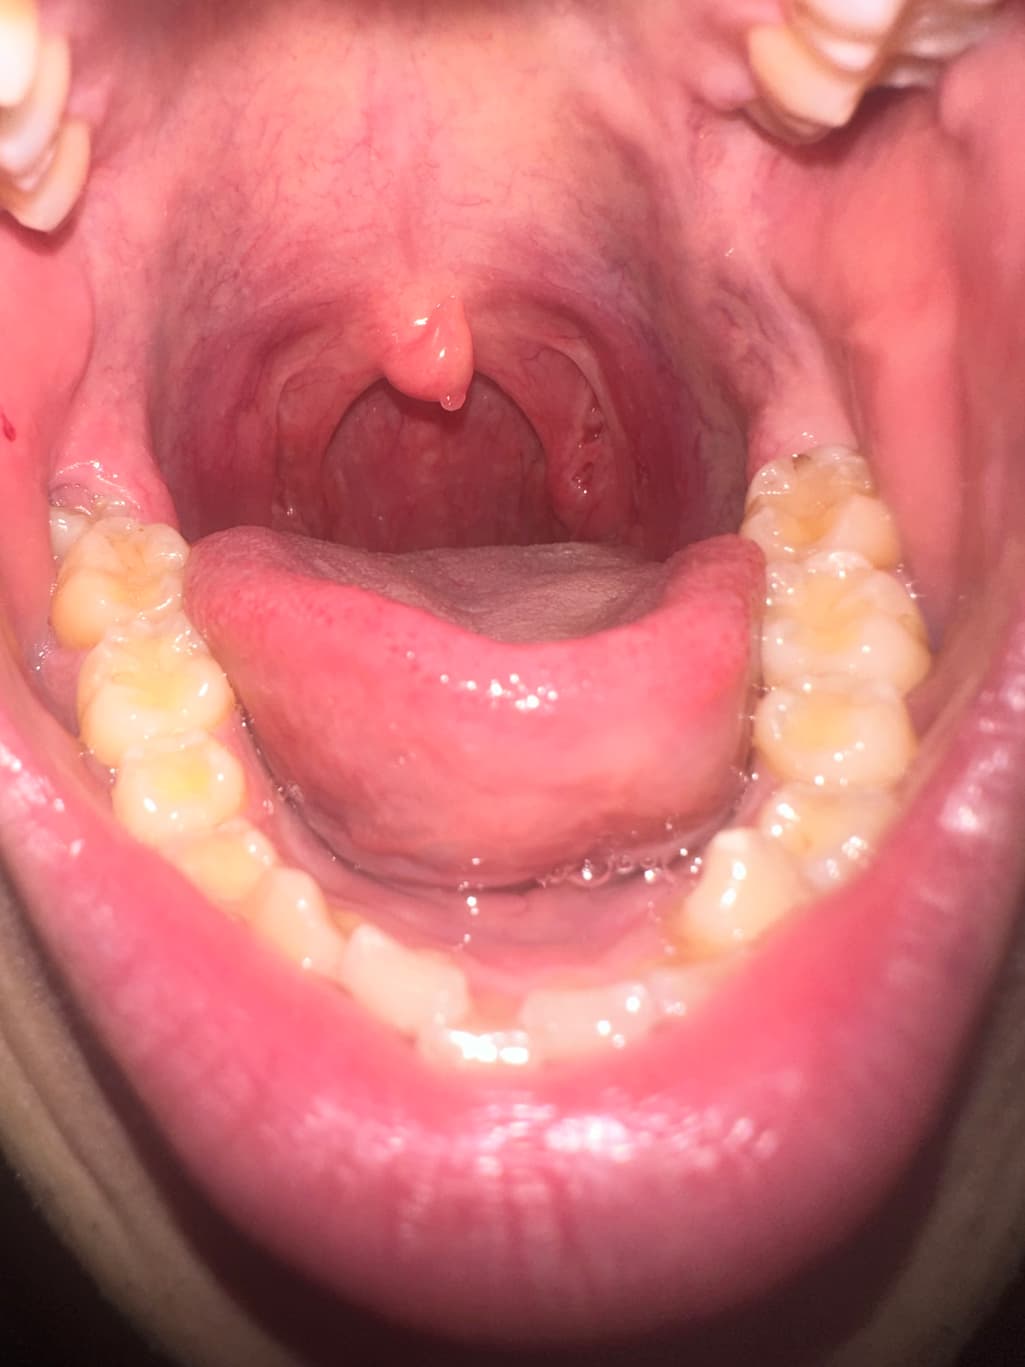

목젖 뒷면 혹이 있어서 확인 부탁드립니다.

올해 1월부터 목젖 뒷면에 혹이 관찰되었습니다.

점점 위치랑 보이는 면적이 변하는것 같아 문의드립니다.

특이소견은 아닌것으로 보여집니다.

굳이 지금 치료하지않고 지켜보셔도 될것같습니다.

안녕하세요. 최성훈 의사입니다.

이비인후과 전문의 진찰 후 경과 관찰로 설명을 들었다면 당장 큰 문제는 아니겠으나 추후 변화 확인을 위해 재진료를 받으시기 바랍니다.